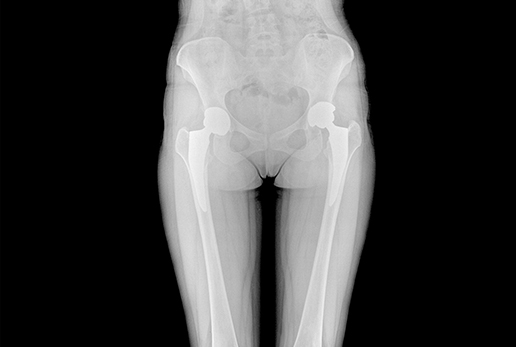

● 核心優(yōu)勢: 大功率 動態(tài)平板 高清攝影 快速成像 透視造影 高清點片

● 采用自主研發(fā)脈沖技術(shù),大尺寸動態(tài)平板,可實現(xiàn)動、靜態(tài)攝影模式無感切換,呈現(xiàn)更優(yōu)質(zhì)的圖像,為臨床醫(yī)生提供診斷依據(jù)。

● 標(biāo)清透視

以較少的輻射劑量呈現(xiàn)醫(yī)生所需的診斷圖像,為臨床初篩提供優(yōu)質(zhì)影像。

● 高清透視

在初診篩查的基礎(chǔ)上,使用高清透視功能輔助醫(yī)生再次確認(rèn)病灶點,降低漏診、誤診的概率。